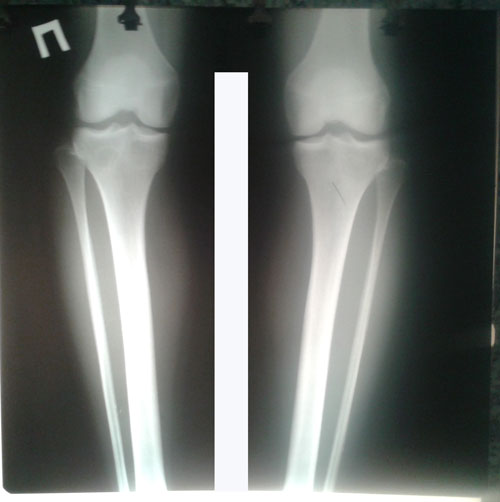

Дата операции 14.07.2017г.

Дата снятия аппаратов 25.09.2017г.

Срок лечения 70 дней.